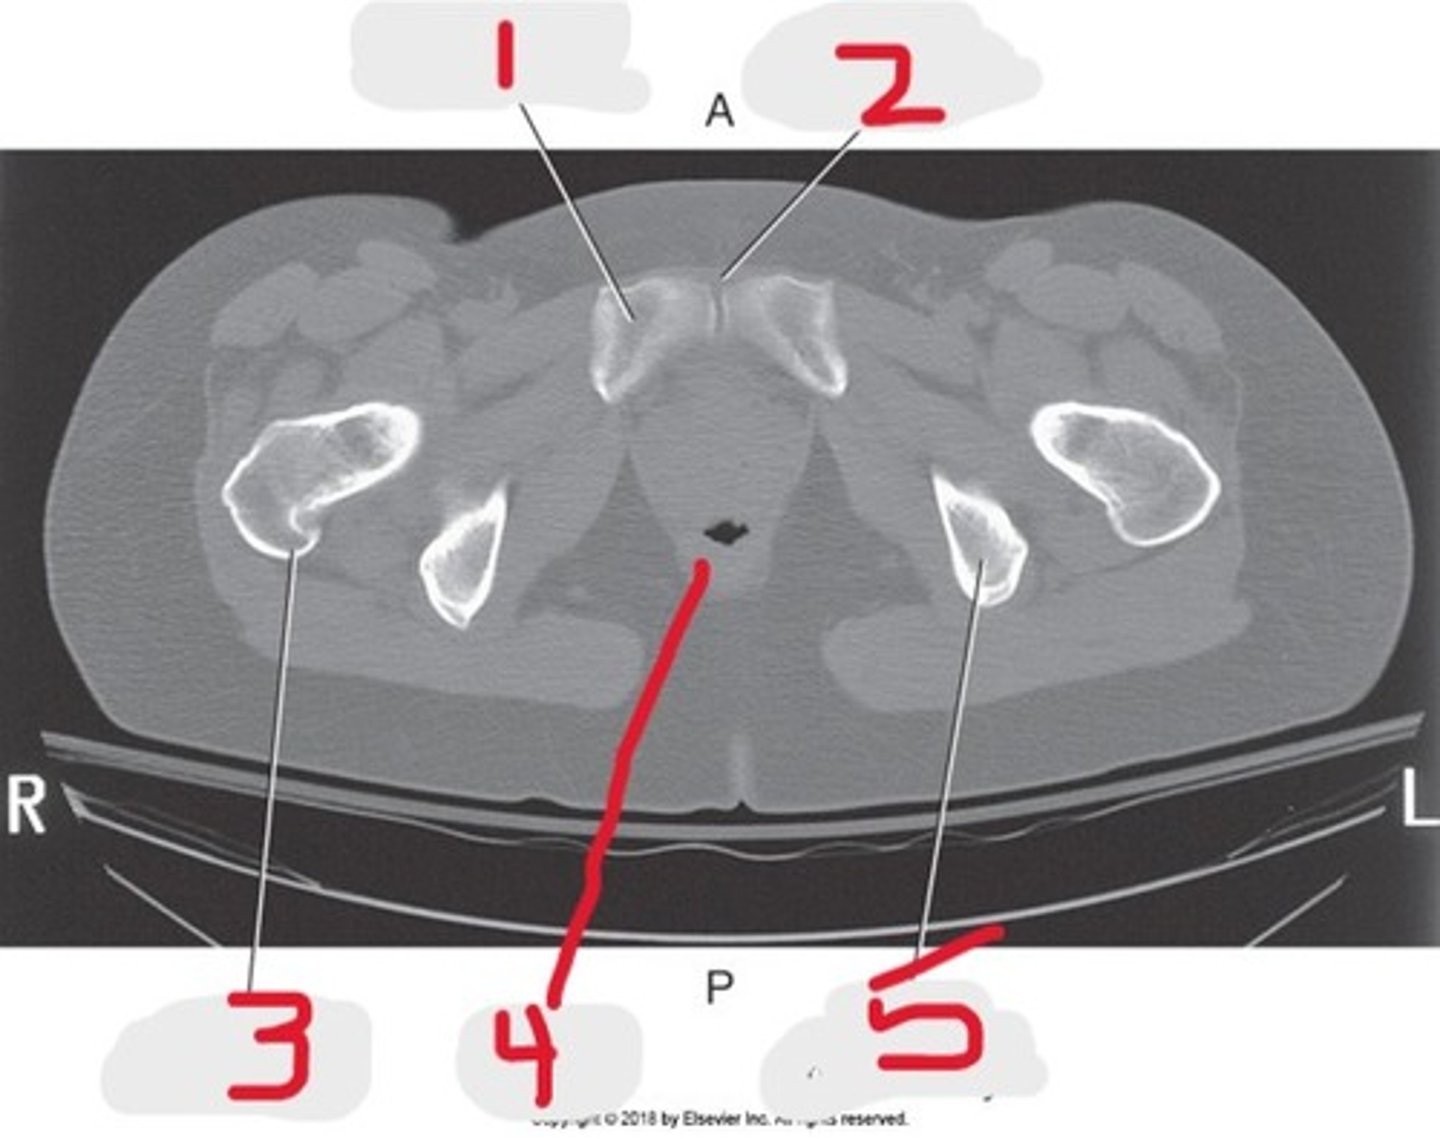

1) Body of pubic bone

2) Pubic symphysis

3) Greater trochanter

4) Anus

5) Ischial tuberosity

Name all numbered structures